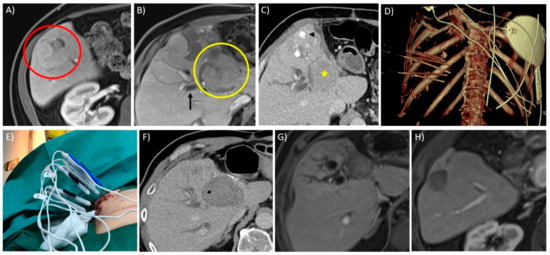

- Schaible, J.; Lürken, L.; Wiggermann, P.; Verloh, N.; Einspieler, I.; Zeman, F.; Schreyer, A.G.; Bale, R.; Stroszczynski, C.; Beyer, L. Primary efficacy of percutaneous microwave ablation of malignant liver tumors: Comparison of stereotactic and conventional manual guidance. Sci. Rep. 2020, 10, 18835. [Google Scholar] [CrossRef] [PubMed]

- Engstrand, J.; Toporek, G.; Harbut, P.; Jonas, E.; Nilsson, H.; Freedman, J. Stereotactic CT-Guided Percutaneous Microwave Ablation of Liver Tumors With the Use of High-Frequency Jet Ventilation: An Accuracy and Procedural Safety Study. Am. J. Roentgenol. 2017, 208, 193–200. [Google Scholar] [CrossRef]

- Kambadakone, A.; Baliyan, V.; Kordbacheh, H.; Uppot, R.N.; Thabet, A.; Gervais, D.A.; Arellano, R.S. Imaging guided percutaneous interventions in hepatic dome lesions: Tips and tricks. World J. Hepatol. 2017, 9, 840–849. [Google Scholar] [CrossRef]

- Rhim, H.; Lim, H.K. Radiofrequency ablation for hepatocellular carcinoma abutting the diaphragm: The value of artificial ascites. Abdom. Imaging 2008, 34, 371–380. [Google Scholar] [CrossRef]

- Rhim, H.; Lim, H.K.; Kim, Y.-S.; Choi, N. Percutaneous Radiofrequency Ablation with Artificial Ascites for Hepatocellular Carcinoma in the Hepatic Dome: Initial Experience. Am. J. Roentgenol. 2008, 190, 91–98. [Google Scholar] [CrossRef]

- Smolock, A.R.; Lubner, M.G.; Ziemlewicz, T.J.; Hinshaw, J.L.; Kitchin, D.R.; Brace, C.L.; Lee, F.T. Microwave ablation of hepatic tumors abutting the diaphragm is safe and effective. Am. J. Roentgenol. 2015, 204, 197–203. [Google Scholar] [CrossRef] [PubMed]

- De Baère, T.; Dromain, C.; Lapeyre, M.; Briggs, P.; Duret, J.S.; Hakime, A. Artificially induced pneumothorax for percutaneous transthoracic radiofrequency ablation of tumors in the hepatic dome: Initial experience. Radiology 2005, 236, 666–670. [Google Scholar] [CrossRef] [PubMed]